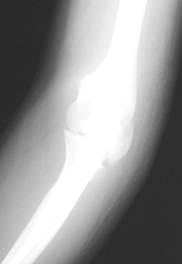

図1 a 初診時レントゲン正面像 図1 b 初診時レントゲン斜位像